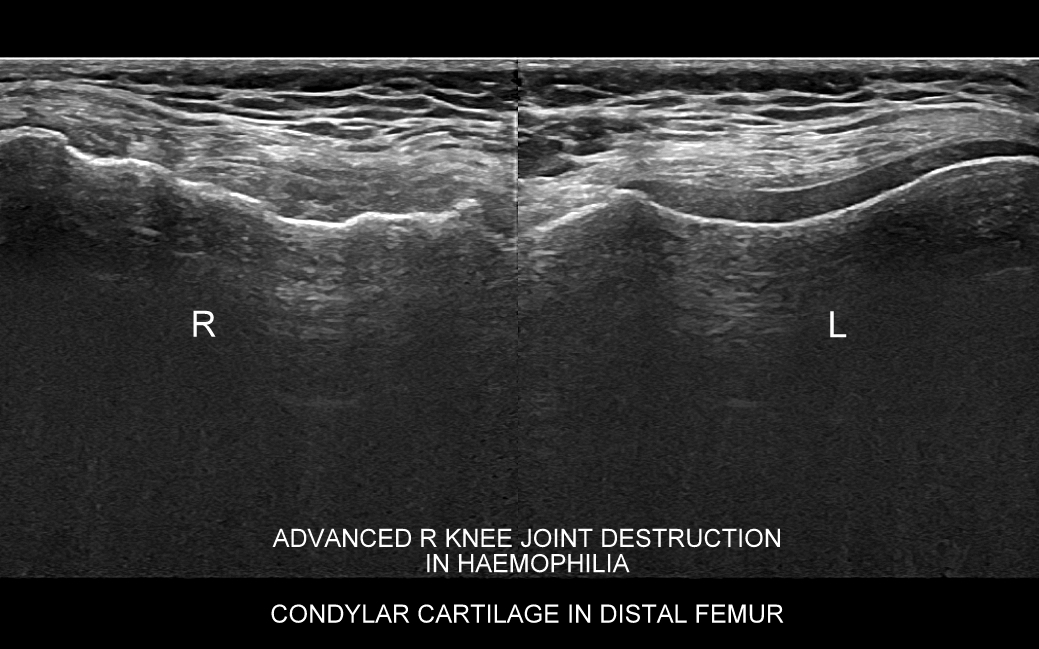

Badanie USG stawu kolanowego ma duże znaczenie w diagnostyce chorób kolan u młodszych i starszych dzieci. Wynika to faktu, iż w tych grupach wiekowych nieskostniała rzepka umożliwia penetrację fal ultradźwiękowych w głąb kolana oraz z charakteru typowych dla dzieciństwa urazów (np. kolano skoczka, choroba Osgood-Schlattera). U dorosłych z kolei USG stawu kolanowego ma ważne zastosowanie przy ocenie przeciążeń, urazów, zapaleń i zwyrodnień zewnętrznych tkanek miękkich stawu, jak np. patologie kaletek, więzadeł pobocznych, czy przyczepów mięśniowych; a także ograniczone zastosowanie w ocenie schorzeń wewnątrzstawowych, takich jak zapalenie i przerost maziówki, uszkodzenia chrząstek szklistych powierzchni stawowych, czy torbiel Bakera.